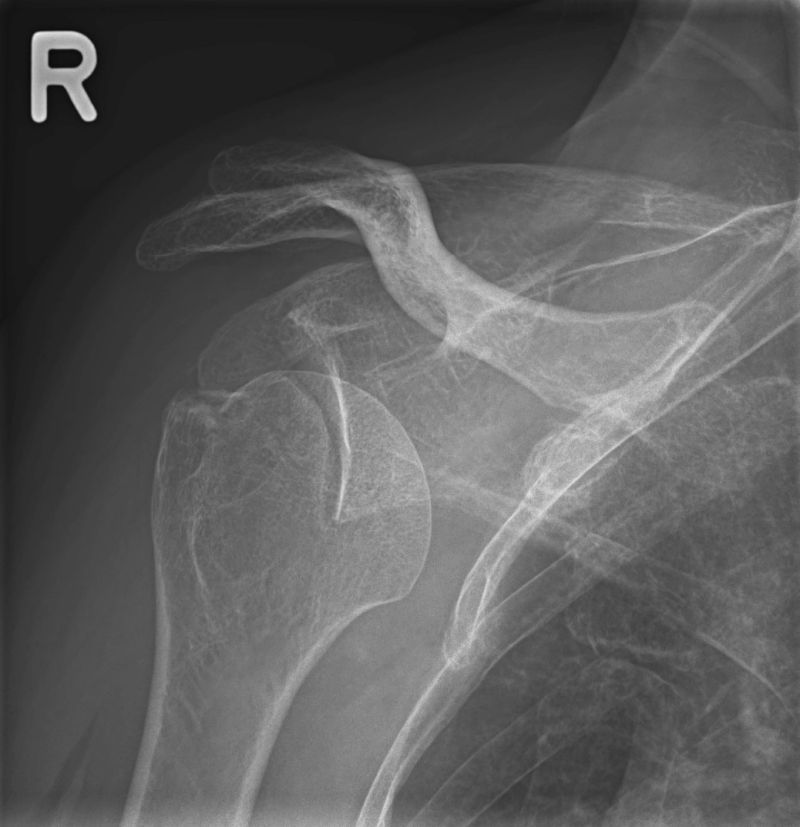

Röntgen des Skeletts und der Gelenke

Das Röntgen hat in der Orthopädie und Unfallchirurgie nach wie vor einen hohen Stellenwert. So können z.B. Knochenbrüche z.B. nach Unfall oder bei Osteoporose gefunden oder ausgekugelte Gelenke festgestellt werden. Ohne viel Zeit zu verlieren kann dann eine für Sie optimale Therapie begonnen werden. Auch das Ausmaß von Verschleißerscheinungen, die Arthrose, kann mit dem Röntgenbild festgestellt werden. In der Rheumatologie werden die Gelenke - meist Hände und Füße - geröngt, um das Ausmaß der entzündlichen Veränderungen am Knochen beurteilen zu können.